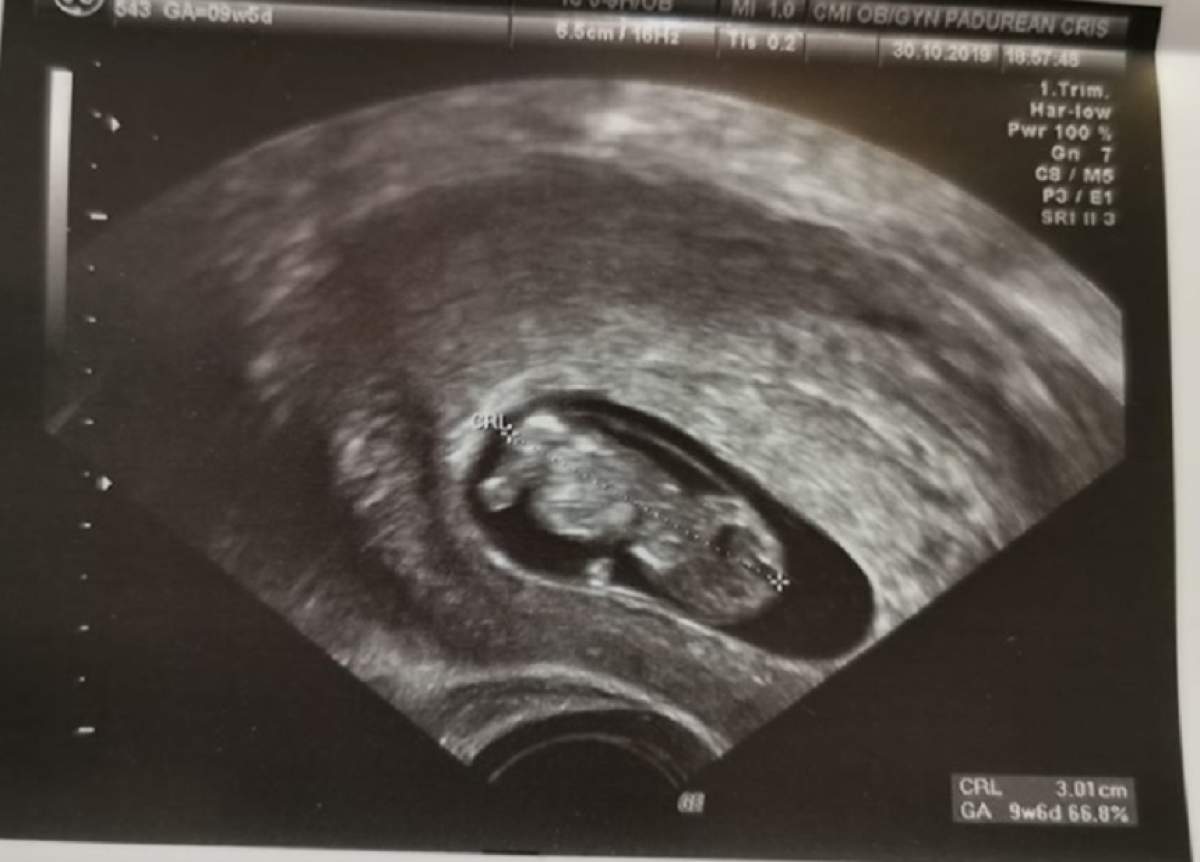

Ionuţ Gabriel, fost concurent în cadrul ultimului sezon MPFM, aşteaptă cu nerăbdare să devină tată pentru prima oară. Soţia lui, Alina, este însărcinată, iar recent au publicat o fotografie cu o ecografie.

Însărcinată în aproape zece săptămâni, Alina speră că este o fetiţă, timp în care Ionuţ vrea băieţel. Un comentariu pe reţelele de socializare a stârnit câteva reacţii.

"Fetiţă", a scris o prietenă de-ale celor doi. "Aşa se vede pe ecografie. Pare fetiţă. N-are faţă de băiat", a completat aceasta.